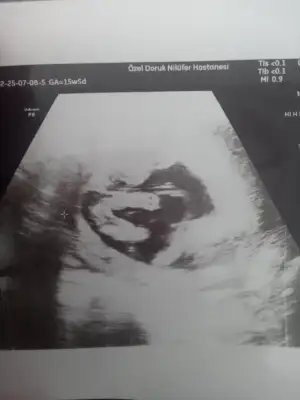

Erkek mi bekliyordu kuzucumkızlar eşimde hala kız olacagına inanamıyor biraz daha bekleym net olması için diyor doktorum net kız dedi

ultrason fotografını da atıyorum simdi

Bencede net kız.kızlar eşimde hala kız olacagına inanamıyor biraz daha bekleym net olması için diyor doktorum net kız dedi